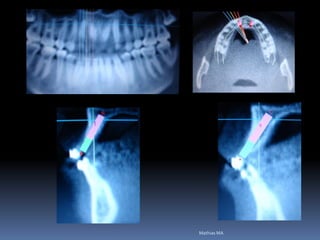

Exames Imaginológicos

Radiografias periapicais, telerradiografias e

panorâmicas;

Tomografias computadorizadas

Softwares de imagens 3D

Guia radiográfico

-posição ótima do implante com marcadores

radiopacos

•Guta percha

•Esferas e tubos metálicos

•Fios e lâminas metálicas

•Lâmina chumbo do RX

•Dentes de sulfato de bário

•Facilita perfuração, paralelismo e distribuição dos

implantes

•Elimina a medição entre implantes

•Permite alternar as possibilidades de instalação

•Vácuo- press ou própria prótese do paciente

duplicada com acrílico transparente

Marcadores radiopacos

Esferas

Tubos

Guia radiológico

Dentes de sulfato de bário

Acetato em vácuo-press

Acrílico com tubos

Acetato com lâmina metálica